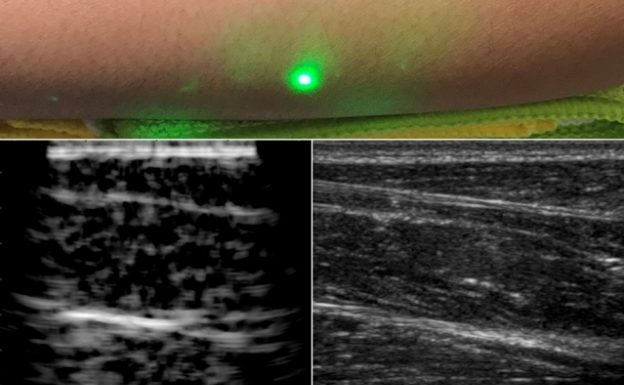

麻省理工(MIT)工程師開發了一種雷射超音波技術,利用對眼睛和皮膚安全的雷射系統,不需碰觸皮膚即可對人體內部進行遠端成像,未來或將能替代傳統超音波使用在特殊需求患者身上。